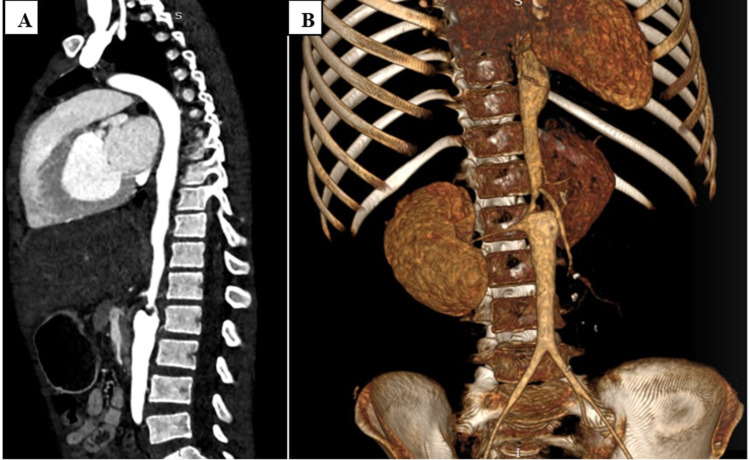

Takayasu arteritis (TA) is a large vessel arteritis that predominantly affects the aorta and its major branches. Its association with tuberculosis (TB) has been described in the literature. This association poses a diagnostic and therapeutic challenge, especially in TB-endemic areas. We report a case of a young Ethiopian female patient who was diagnosed with TA associated with TB. We discuss the diagnostic and therapeutic challenges of this association.